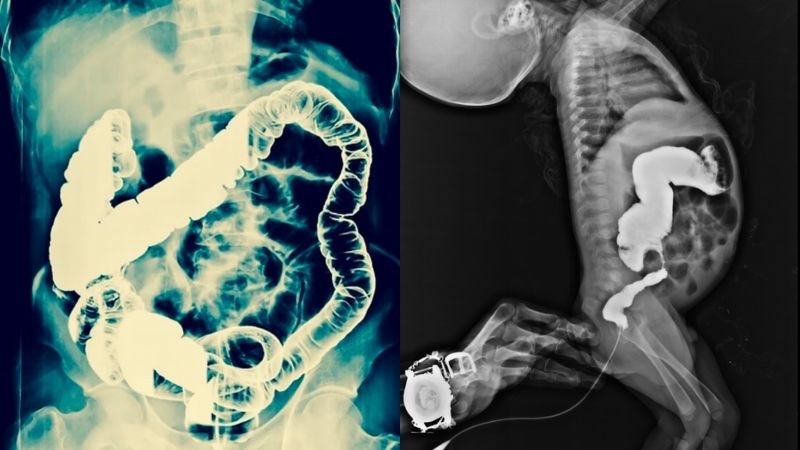

- Chụp X-quang cản quang đường tiêu hóa: chụp đại tràng có thể thấy đoạn ruột giãn phía trên đoạn vô hạch.

X quang bụng là cận lâm sàng có giá trị cao giúp bác sĩ chẩn đoán bệnh